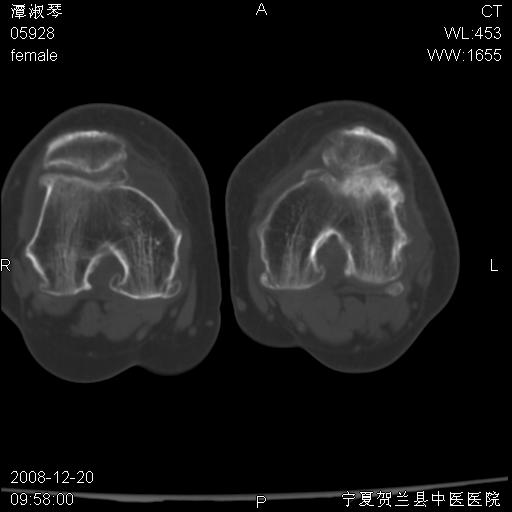

标题: CT17526:请各位看看是啥?

支持骨梗死,退行性骨关节病,膝关节积液.

考虑骨梗死可能性大

骨梗死可能性大

左股骨下段骨梗死。双膝退变。

左胫骨下端松质骨及髓腔内可见点片状高密度灶,骨皮质无明显膨胀及变薄。病变范围较长。支持骨梗死,退行性骨关节病,膝关节积液